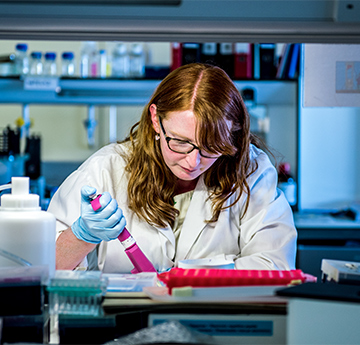

Clefyd cardiofasgwlaidd (CVD) yw achos mwyaf marwolaethau yn y byd. Mae ein rhaglenni ymchwil amlddisgyblaethol yn datblygu gwybodaeth uwch am achosion, atal a thrin clefydau myocardaidd a fasgwlaidd er budd cleifion.

Mae ymchwil clefyd cardiofasgwlaidd a wneir gan yr Ysgol Feddygaeth yn cael ei ariannu a'i gefnogi gan Sefydliad Prydeinig y Galon Cymru sy'n golygu ei fod yn ganolfan ar gyfer yr ymchwil hon yng Nghymru.